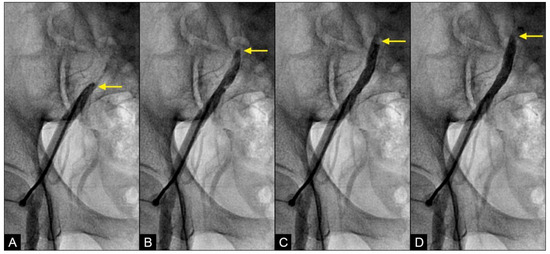

VORTEX formation and degeneration: With the novel angiographic protocol, we observed the following phenomena in the iliac artery during systole: At first, the blood (depicted in white) flowed in an antegrade direction, exhibiting a pointed tip of laminar flow that followed the apical curve of the artery (white arrow) (Figure 10A,B). Subsequently, the pointed tip of the blood flow halted abruptly, with all layers recoiling like a collapsing stack of dominoes (white arrow) (Figure 10C). The tip of the flow then twisted and turned on itself, resembling a vortex (white arrow) (Figure 10D). Sixty-seven milliseconds later, this motion dissipated and was replaced by a mass of black contrast (arrowhead) moving in a retrograde direction along the inner curve (Figure 10E). This black contrast mass gradually expanded, indicating the superior strength of the retrograde flow (Figure 10F). The sharp interface between the blood (white) and the contrast (black) suggested a soft contact between the two liquids (Video S3).

Figure 10.

(A–C) Vortex formation in the iliac artery. This is a sequence of six consecutive angiographic images of the iliac artery. (A) The iliac artery is filled with contrast (in black). (B) Sixty-seven milliseconds later, the blood (homogenously white) is seen moving down with a sharp tip of laminar flow (white arrow). (C) Subsequently, the pointed tip of the blood flow halted abruptly, with all layers recoiling like a collapsing stack of dominoes (white arrow). (D) The tip of the flow then twisted and turned on itself, resembling a vortex. (E,F) This vortical motion dissipated and was replaced by a mass of black contrast (arrowhead) moving in a retrograde direction along the inner curve (black arrow).